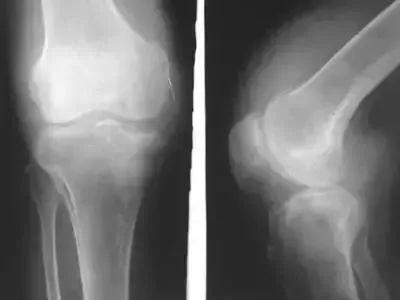

一天两万步,膝关节积液

张阿姨今年五十多岁了。她通常喜欢锻炼。她经常去附近的公园散步,基本每天走两万步。没想到,这种追求健康的方式给她带来了很大的麻烦。

正是因为走的太多,膝盖才受损。时间长了,本该润滑关节的关节腔液越来越多,导致积液。